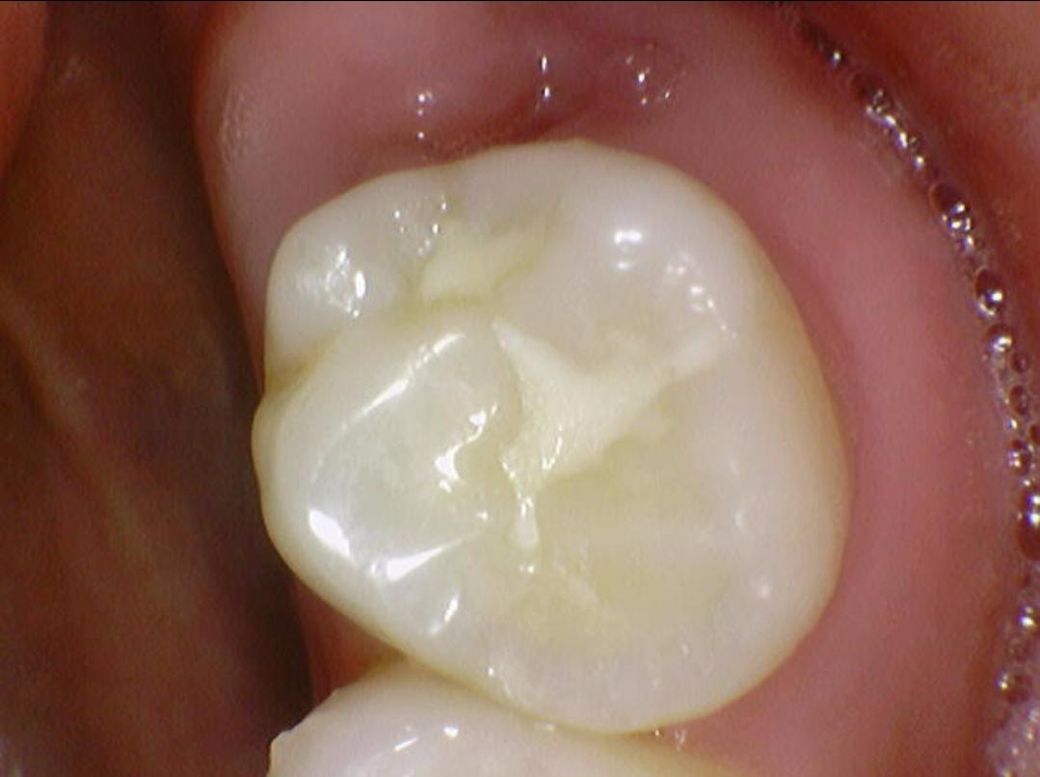

밑에 구강내부 사진(16,17,26,27번 치아)들에서

치료가 반드시 필요한 치아는 몇번째 사진 이런식으로 설명 부탁드립니다

• 3번 째 사진

• 4번 째 사진